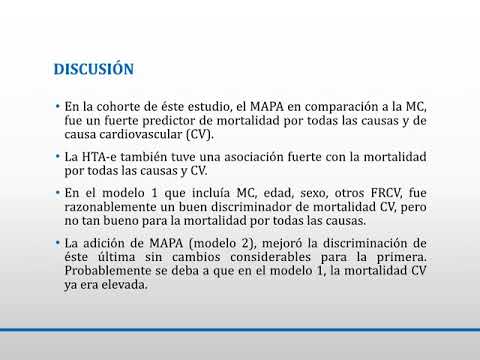

Relación entre la medición ambulatoria o nosocomial de la TA y la mortalidad. Dra. Carolina Reynoso. Residencia de Cardiología. Hospital C. Argerich. Buenos Aires

Relación entre la medición ambulatoria o nosocomial de la presión arterial y la mortalidad. Dr- Alejandro Kim. Residencia de Cardiología. Hospital C. Argerich. Buenos Aires